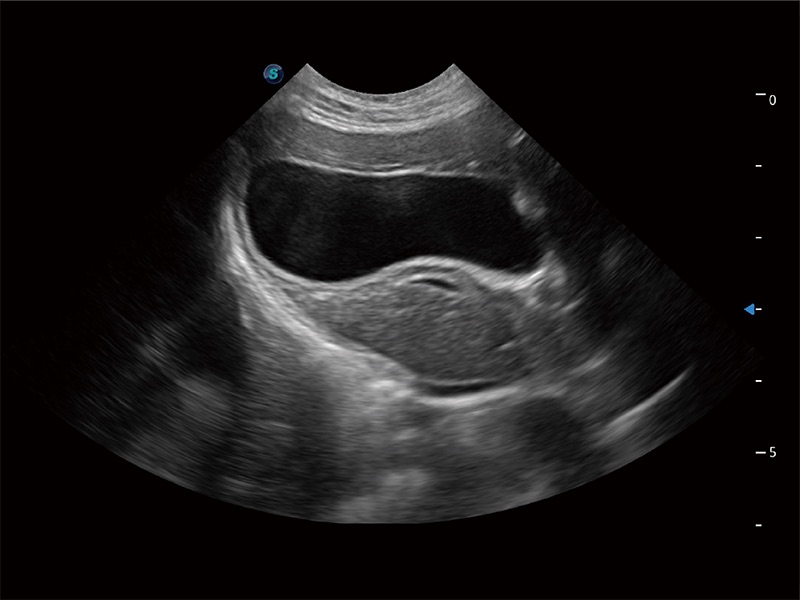

(猫)胆囊